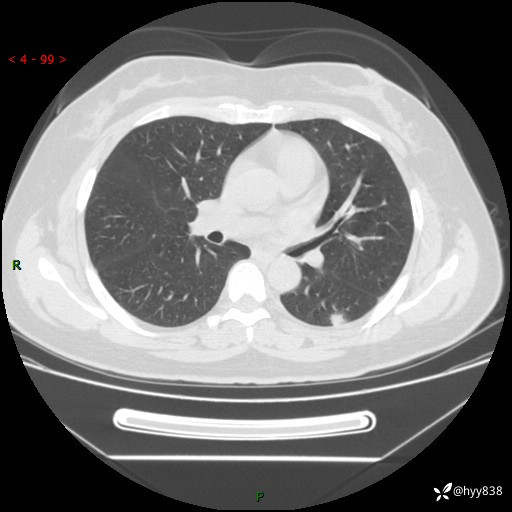

胸部CT复查+增强(2024.6)